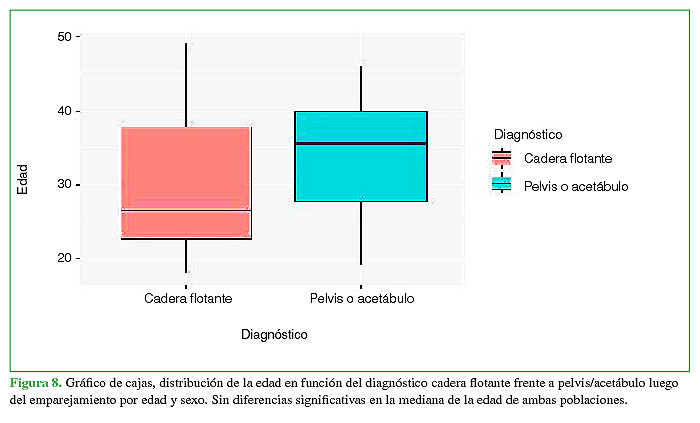

Entonces, solo se incluyó en la comparación un subgrupo de 86 pacientes de los cuales 23 eran del grupo de CF y 63, del grupo pelvis/acetábulo, sin diferencias estadísticamente significativas entre las distribuciones de edad (p = 0,054) y sexo (p = 0,15) (Figura 8).